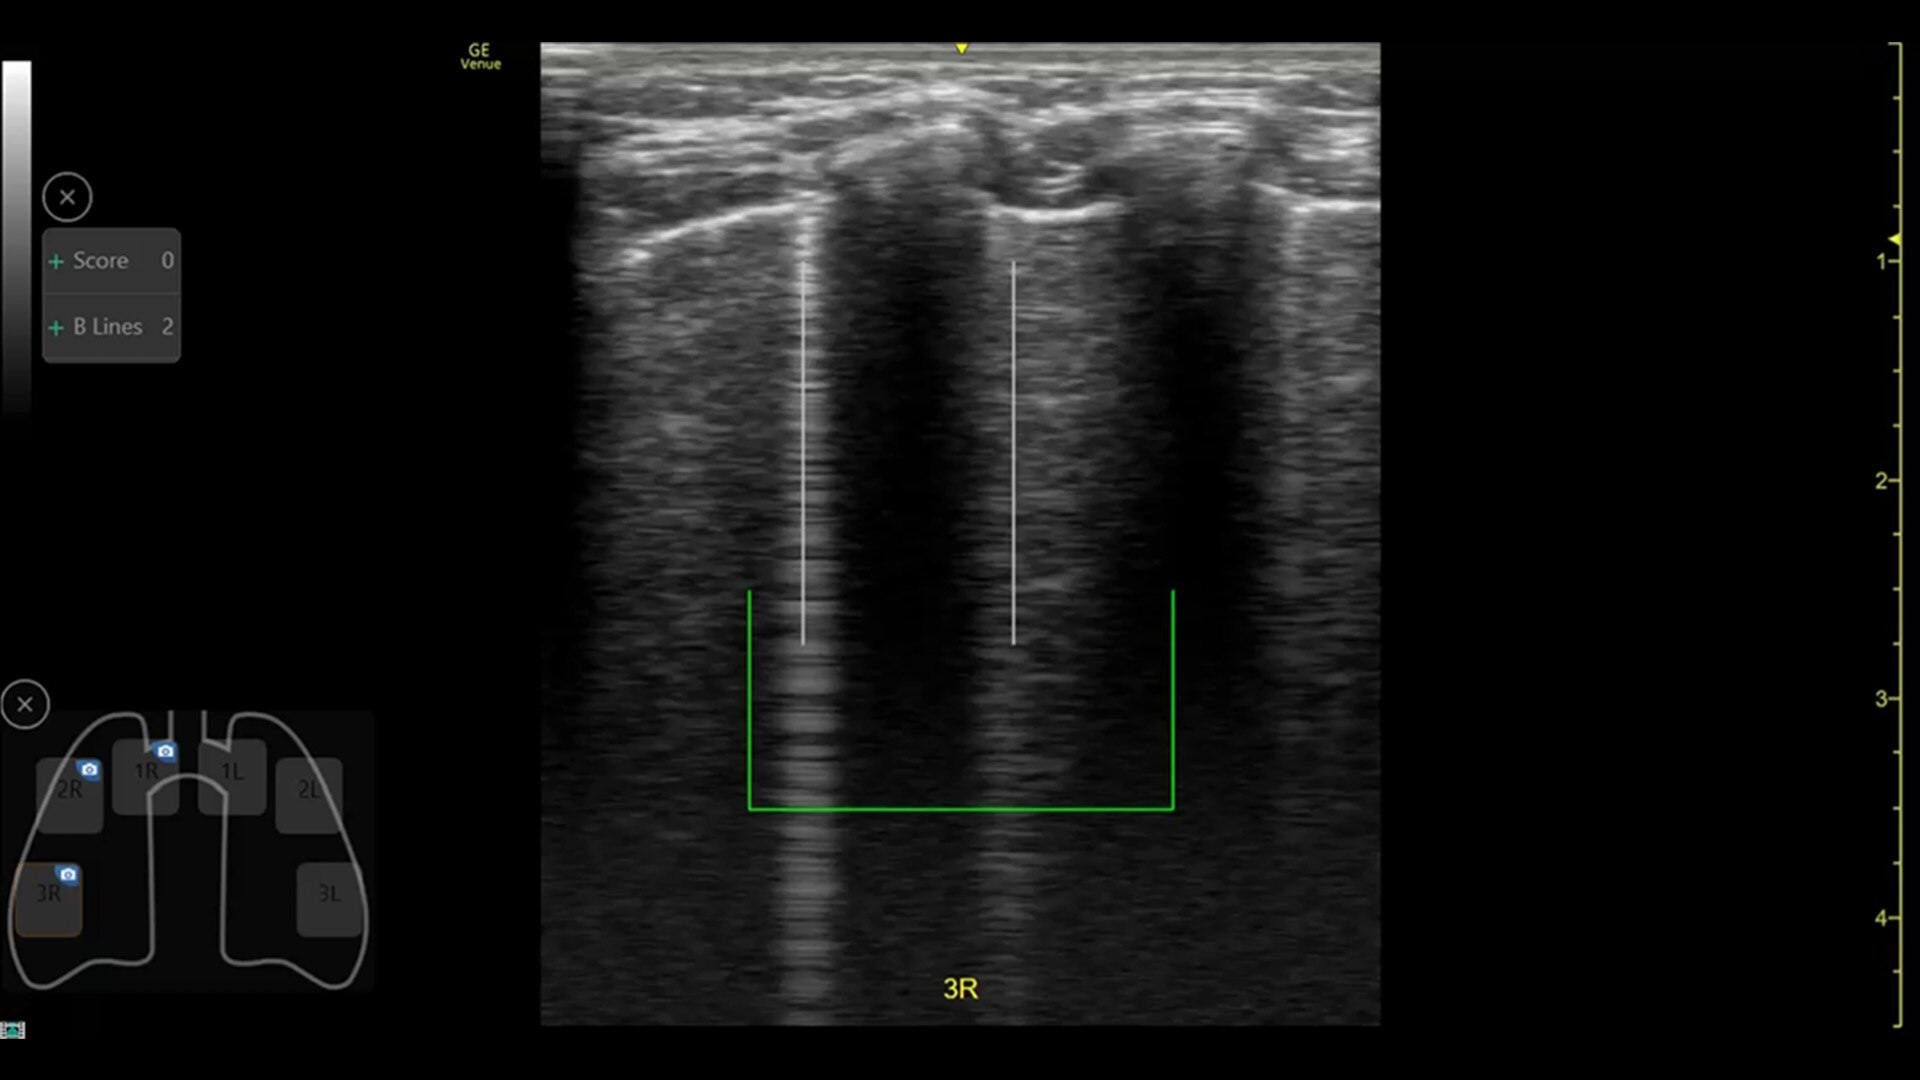

AI-DRIVEN AUTO TOOLS

Advanced and automated clinical tools enabling you to quickly diagnose, treat and determine a care pathway.

Venue Go has been designed and tested to be walk up easy for novice to expert users, and it features a number of AI-enabled automated tools to accelerate clinical workflow while also reducing the fatigue of repeated and difficult tasks. Utilizing proprietary algorithms, we synthesize data from numerous patients to ensure accurate calculations for clinical confidence.

REAL-TIME EF

For accurate, instant, and rapidly updating results

Capture precise results instantly without requiring ECGs—thanks to Real-Time EF, an AI tool that continuously calculates real-time ejection fraction during live scanning in apical 4CH view. And for improved accuracy, its integrated quality indicator helps users select an optimal view for generating exacting results. Reducing the time it takes to reach a result while helping provide consistency, a study found that Real-Time EF results are within ±10 points of experts in 86% of adult cases (80% including pediatrics).2